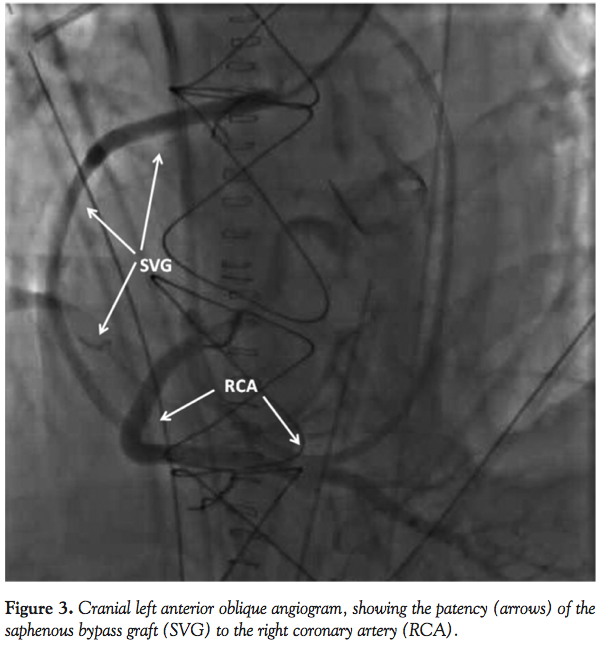

At the time of his presentation, the patient was found to have a blood pressure of 90/50 mm Hg and a heart rate of 110 bpm in sinus rhythm. Vasopressors and inotropes were adjusted and we started the procedure by placing a right radial artery 6 Fr sheath. During coronary angiography, the standard 5 Fr Judkins left (JL) 3.5 catheter failed to selectively engage the ostium of the Cabrol conduit, so we changed to an Amplatz left (AL) 2 catheter, which enabled a better cannulation. After extensive catheter manipulation, the 6 Fr AL 2 catheter engaged the Cabrol conduit ostium slightly better and the first angiograms showed a diffuse stenosis of the Gore-Tex graft to the left main starting at the site of the coronary aorta-anastomosis with impaired distal flow around the left coronary system (Figures 2A and 2B). Then, the saphenous bypass graft to the right coronary artery was cannulated, showing its patency (Figure 3).